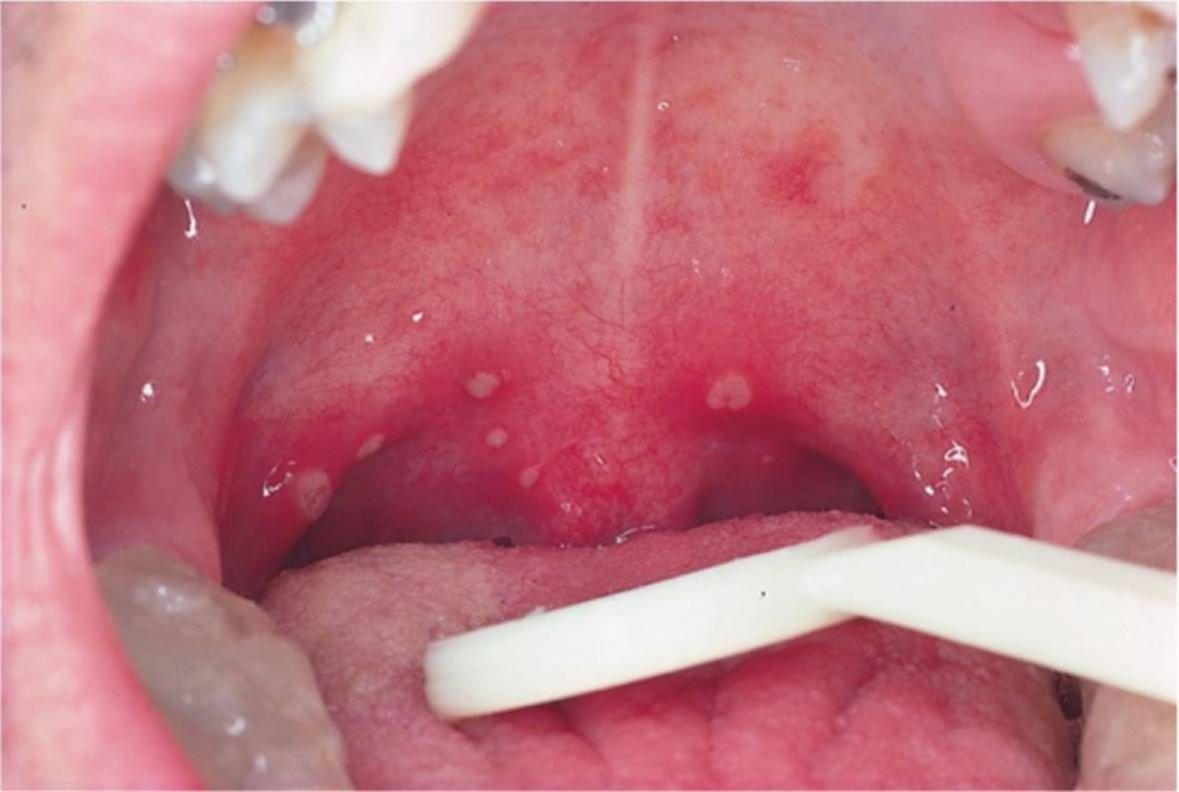

Las manifestaciones en las mucosas se conocen con el nombre de enantema. El mismo tiene su equivalente en la piel: el exantema. Se trata de lesiones variadas, tipo máculas (manchas rojizas), pápulas (sobre elevamiento de la piel como una roncha) y lesiones de tipo urticarianas distribuidas en todo el cuerpo.Constituye un grupo de lesiones muy variadas e inespecíficas que lesionan la mucosa (por ejemplo, de la boca) y pueden causar dolor al tragar (odinofagia). Por este motivo, la aparición de enantema en pacientes con COVID-19 reportada por diversas sociedades y asociaciones científicas de dermatología y alergia en todo el mundo obligó a reconsiderar las formas de presentación y los signos y síntomas asociados con esta enfermedad pandémica.

PRINCIPALES SINTOMAS DEL COVID-19: fiebre, dificultad respiratoria, tos, odinofagia, pérdida del olfato (anosmia) y pérdida del gusto (disgeusia). Por eso, es muy importante tener presente la aparición de enantema y de exantema en un paciente con otros signos y síntomas asociados o aun cuando se presentan en forma aislada.